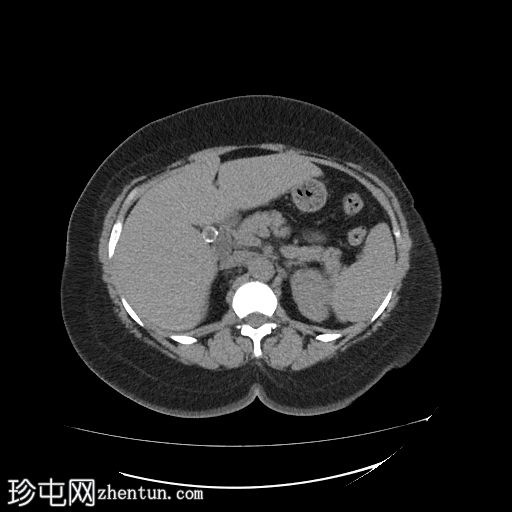

冠状位

平扫

胆囊内可见多发大小不一的多面环状钙化胆结石。胆总管直径处于正常上限。胆总管内未见其他结石。

右侧肾中盏可见一非梗阻性结石(10.5 mm),CT值较高(900–1000 HU)。

钙化胆囊结石相对于胆汁呈高密度,因此是唯一能在CT图像上清晰显示的结石类型。在CT图像上,大部分胆固醇结石相对于胆汁呈低密度,而其他类型的胆结石与胆汁呈等密度,这些结石在CT图像上可能无法清晰显示。

右肾中盏可见高密度肾结石(900–1000 HU),提示为含钙硬结石,可能为草酸钙一水合物。